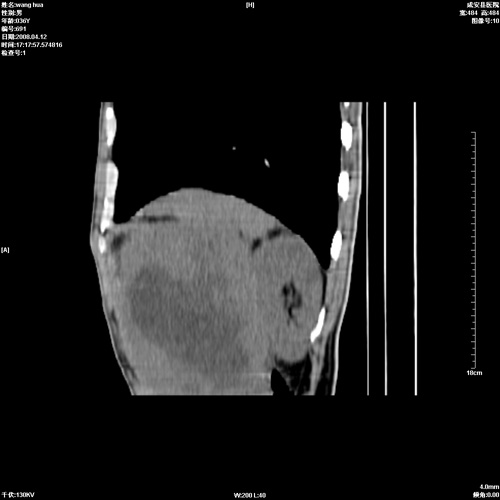

标题: CT12809:男36岁,自感上腹胀5天,B超诊断为脾肾之间占位,血 [打印本页]

标题: CT12809:男36岁,自感上腹胀5天,B超诊断为脾肾之间占位,血

请各位老师先分析一下定位 明天做增强

脾脏明显增大,其内见巨大低密度灶,境界不清,病史较短,考虑恶性病变脾血管内皮细胞肉瘤可能。建议增强扫描与脾脏淋巴瘤及血管瘤鉴别。